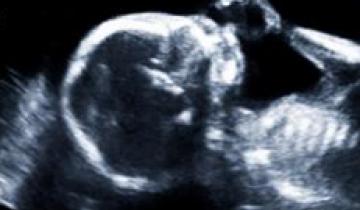

Cerebral Palsy is the most common motor disability in children caused by abnormal development or damage to the motor area of the brain’s outer layer (called the cerebral cortex), the part of the brain that directs muscle movement. This damage can occur before, during, or shortly after birth.

MRI of brain showing damage